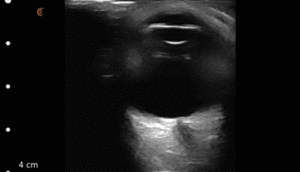

Point of care ultrasound of the IVC (inferior vena cava) is a non-invasive means of volume assessment in the critically ill. While no one study has been able to quantify exactly where to measure or make the assessment, the IVC can be assessed in a fat or flat paradigm.

In the video below, ultrasound educator Chris Eddy uses the Clarius portable ultrasound scanner to assess the IVC for volume status.

He examines the walls of the IVC to ensure that they move during respiration and are not coming in contact with each other (which could be indicative of a flat IVC). He also looks for any respiratory motion which tends to dissipate in a volume overload status.